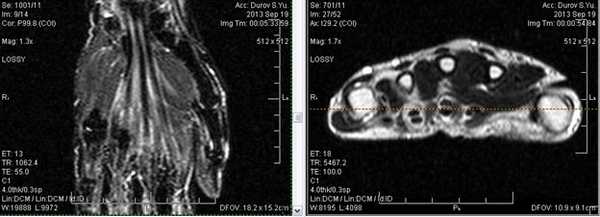

МРТ показывает веретенообразное расширение нерва, которое вызвано утолщением нервных пучков и жировой и фиброзной пролиферацией. МРТ характеристики фибролипоматозной гамартомы являются патогномоничным, что исключает необходимость в биопсии для диагностики.

Клинически: Отек левой руки, сохраняющийся длительное время, в настоящий момент пациент начал жаловаться на нарушение чувствительности боковых трех пальцев.